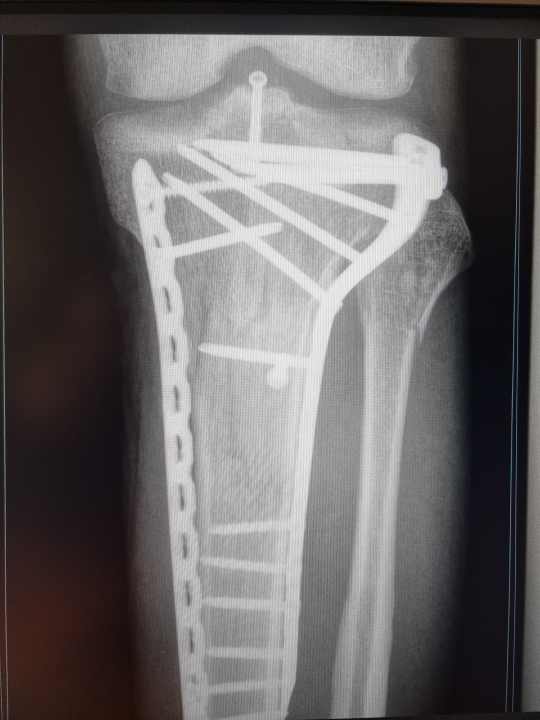

After a fall left me with a shattered tibial plateau and no functioning anterior cruciate ligament, I am at high risk of further knee problems. Over the years, doctors and therapists have given me very different advice. It seems that everyone says something different about mountain biking as a knee patient. The stresses involved in biking are quite complex. Finding a real expert is not that easy. - Jan Timmermann, BIKE editor

Injuries caused by falls are speed-dependent and can include complex bone fractures, for example. Another problem when falling on the knee is the weight. Since the spread of e-MTBs, the increase in tibial plateau fractures (fracture of the tibial plateau, editor's note) has been striking. These are relatively severe for the knee joint because they are often associated with injury to ligaments and capsules. With a heavier bike, the forces are naturally higher. If you factor in the generally higher speed of e-bikes, the load increases exponentially.

In principle, the aim of the rehabilitation process should be to regain as much mobility as possible. This is not always easy with a serious injury such as a tibial plateau fracture. This is no longer a bumped mudguard, but a severe impairment of the static situation and joint mechanics in the knee. Anyone with an injury should definitely try to maintain the joint's range of motion for as long as possible. For example, an extension deficit of five degrees should not be allowed to gradually increase to ten or even 15 degrees. The body then reacts with compensatory movements in the hip or pelvis and movement sequences are no longer executed in a functionally correct manner, which then indicates problems in other parts of the body.